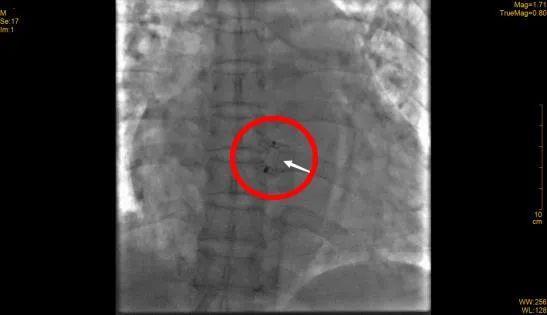

徐先增团队顺利为患者放入封堵器

完善相关检查后,徐先增团队为农先生实施了介入封堵术。仅40分钟,他们便顺利将封堵器放入异常通道并将其固定。经查,农先生的右主动脉、右心室已恢复“泾渭分明”的状态。

徐先增团队正在实施介入封堵术